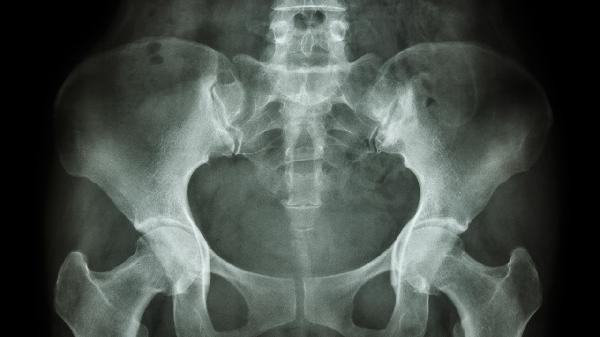

外翻X线表现与测量包括哪些

外翻X线表现与测量主要包括足部力线偏移、跖骨间角度增大、第一跖趾关节半脱位、籽骨位置异常及前足横弓塌陷等指标。

外翻在X线下表现为第一跖骨内翻与拇趾外翻形成的异常力线。通过测量拇外翻角可量化畸形程度,正常值小于15度,超过20度提示病理改变。典型特征包括第一跖骨内侧骨赘形成,第二趾可能发生锤状趾变形。

第一、二跖骨间角在X线正位片上超过9度即为异常。角度增大程度与畸形严重性相关,中度畸形为10-15度,重度可达20度以上。常伴随第一跖骨旋前及第二跖骨头下胼胝体形成。

关节匹配度可通过关节面夹角评估,正常小于7度。半脱位时可见近节趾骨基底向外侧移位,关节间隙不对称增宽,后期可能出现关节边缘骨赘增生或软骨下骨硬化等退行性改变。

籽骨系统位置通过籽骨分级评估,正常位于第一跖骨头下方。外翻时可见腓侧籽骨外移,严重者完全脱位于跖骨间隙。籽骨移位可导致屈拇肌腱力臂改变,加重畸形进展。

通过测量跖骨头连线与地面的夹角评估横弓形态,塌陷时角度增大。X线侧位片可见第二、三跖骨头下沉,可能伴发转移性跖痛症。晚期病例可能出现跖趾关节背侧半脱位。